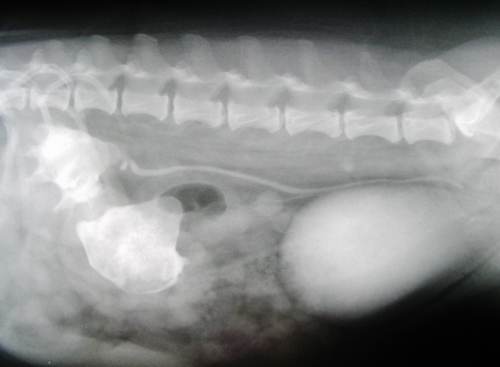

下の二枚の写真は6歳のウエル・シュコーギーでみられた両側性の巨大な腎結石のレントゲン写真です。「おにぎりのような三角形」のような2つの大きな塊が腎結石で、腎結石は腎盂(つくられた尿が溜まる場所)をほぼ占拠して腎臓を内側から強く圧迫していました。

写真は静脈性尿路造影のもので、腎臓から膀胱に白い筋状にみえる尿管と白い卵型に見える膀胱も一緒に造影されて写っています。この腎結石は将来的な腎機能不全のリスクが高いため、両側とも手術により摘出いたしました。ここまで結石が大きく育つのは稀なことですので、腎結石の極端な例としてご覧ください。